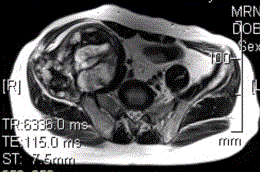

患者男,28岁,右下腹及臀部疼痛5个月余。查体:右髂骨外后侧压痛,右下腹可触及一软组织包块,质韧,固定。行骨盆正位CR、骨盆CT及MR扫描见下图。...

问题 患者男,28岁,右下腹及臀部疼痛5个月余。查体:右髂骨外后侧压痛,右下腹可触及一软组织包块,质韧,固定。行骨盆正位CR、骨盆CT及MR扫描见下图。 关于病变发生的部位,叙述正确的是

选项 A.右髂骨皮质部,累及右侧腰大肌 B.右髂骨髓质部,累及右髂骨皮质及右侧腰大肌 C.右侧腰大肌,累及右髂骨 D.盲肠,累及右髂骨 E.末段回肠,累及右髂骨

答案 B